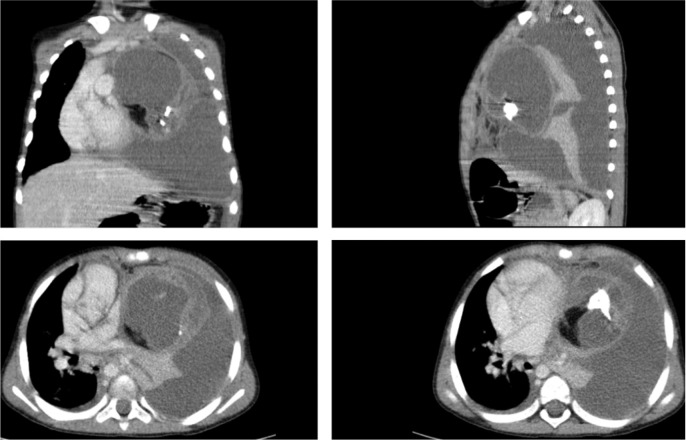

Teaching point: This is a review of the typical radiological features of a mature mediastinal teratoma with a rare presentation of spontaneous pleural rupture.

Abstract Image